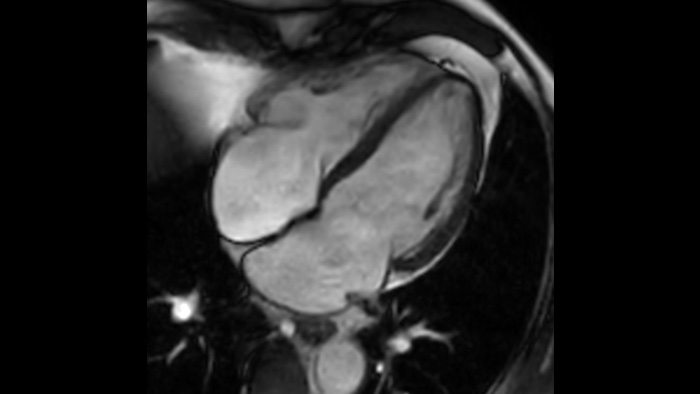

Ahora puede tenerlo todo con Ingenia Ambition. Ofrece la oportunidad de mejorar sus imágenes de resonancia magnética en todos los niveles.

Confianza diagnóstica Ofrece una resolución espacial hasta un 60% más alta en el mismo tiempo de escaneo. 4

Confianza diagnóstica Amplíe su capacidad de obtener imágenes excelentes en todas las áreas clínicas. Vea cómo se benefician sus compañeros.